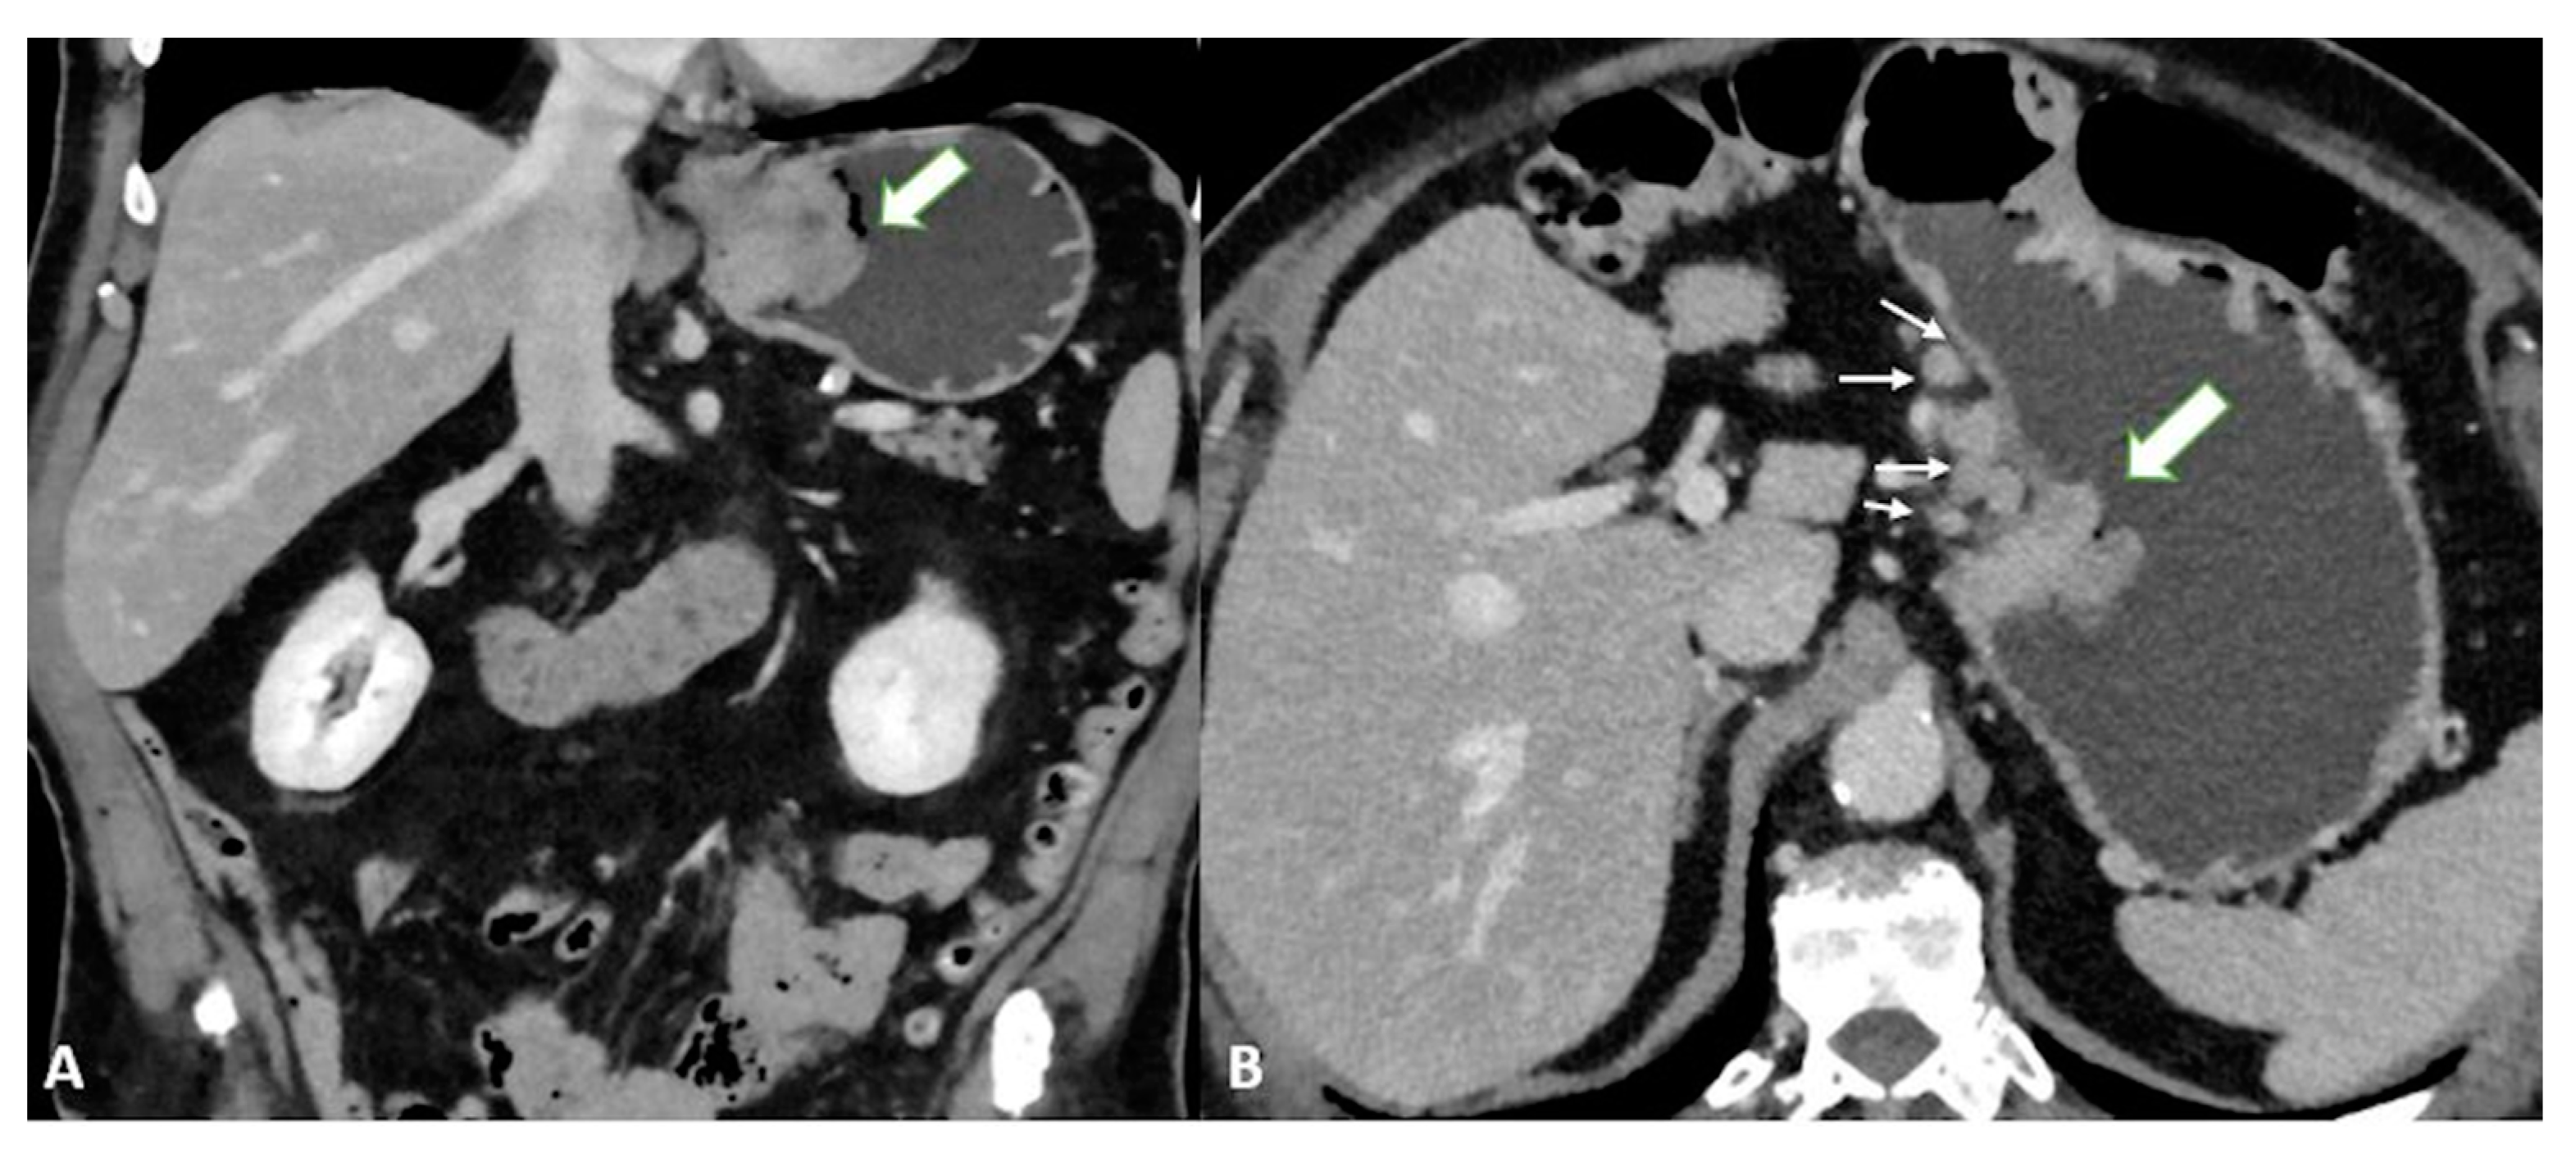

T3 tumors have a subserosal invasion, and discrimination between a gastric mass and the outer layer can be difficult: small linear strandings in the gastric fat, due to a desmoplastic reaction, can be confused with serosal involvement (Figure 2 and Figure 3).

Figure 2.

T3 gastric cancer in a 72-year-old male patient. (A) Axial 2D image in the portal venous phase and (B) Coronal 2D reconstruction showing wall thickening (white arrow) in the lesser curvature of the low body of the stomach and inhomogeneous enhancement. The tumor invades the subserosa layer without invasion of the serosa and adjacent structures.

Figure 3.

T3 gastric cancer in a 74-year-old female patient. (A) Coronal 2D reconstruction in the portal venous phase and (B) Axial 2D image showing (thick arrows) enhanced wall thickening in the lesser curvature side of the high body of the stomach. (B) also shows a cluster of pathologic round lymph nodes adjacent to the gastric cancer (thin arrows). The tumor invades the subserosa layer without invasion of the serosa and adjacent structures.

Finally, T4a also demonstrates serosal involvement, which makes the differential with T3 very difficult. This is especially true because the gastric serosa is not well defined due to the different amounts of subserosal adipose tissue. To solve the differential, T4a frequently shows solid nodules or band-like stranding in the perivisceral adipose tissue (Figure 4).

Figure 4.

(A) Axial 2D image in the portal venous phase of a T4a gastric cancer in a 66-year-old female patient. The tumor (thick arrow) is the enhanced wall thickening in the lesser curvature side of the middle body of the stomach which penetrates the serosa with some solid deposits (white asterisk) in the perivisceral fat tissue and some pathologic lymph nodes (thin arrow) with necrotic-colliquative components inside. (B) Axial 2D image of a T4a gastric cancer in a 78-year-old female patient. The tumor (thick arrow) is the enhanced wall thickening on the lesser curvature side of the low body of the stomach which penetrates the serosa with some spiculatures in the perivisceral fat tissue and a pathologic lymph node (black asterisk).